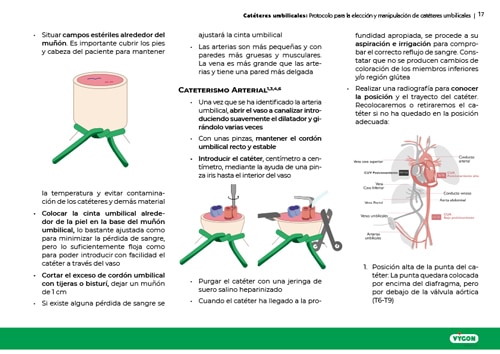

El uso del cateterismo umbilical es una práctica usual en las unidades de cuidados intensivos neonatales. Su aplicación en la atención a recién nacidos ha ido variando y ajustándose a las demandas de los pacientes y al desarrollo de nuevas tecnologías y procedimientos en el campo de los cuidados neonatales.